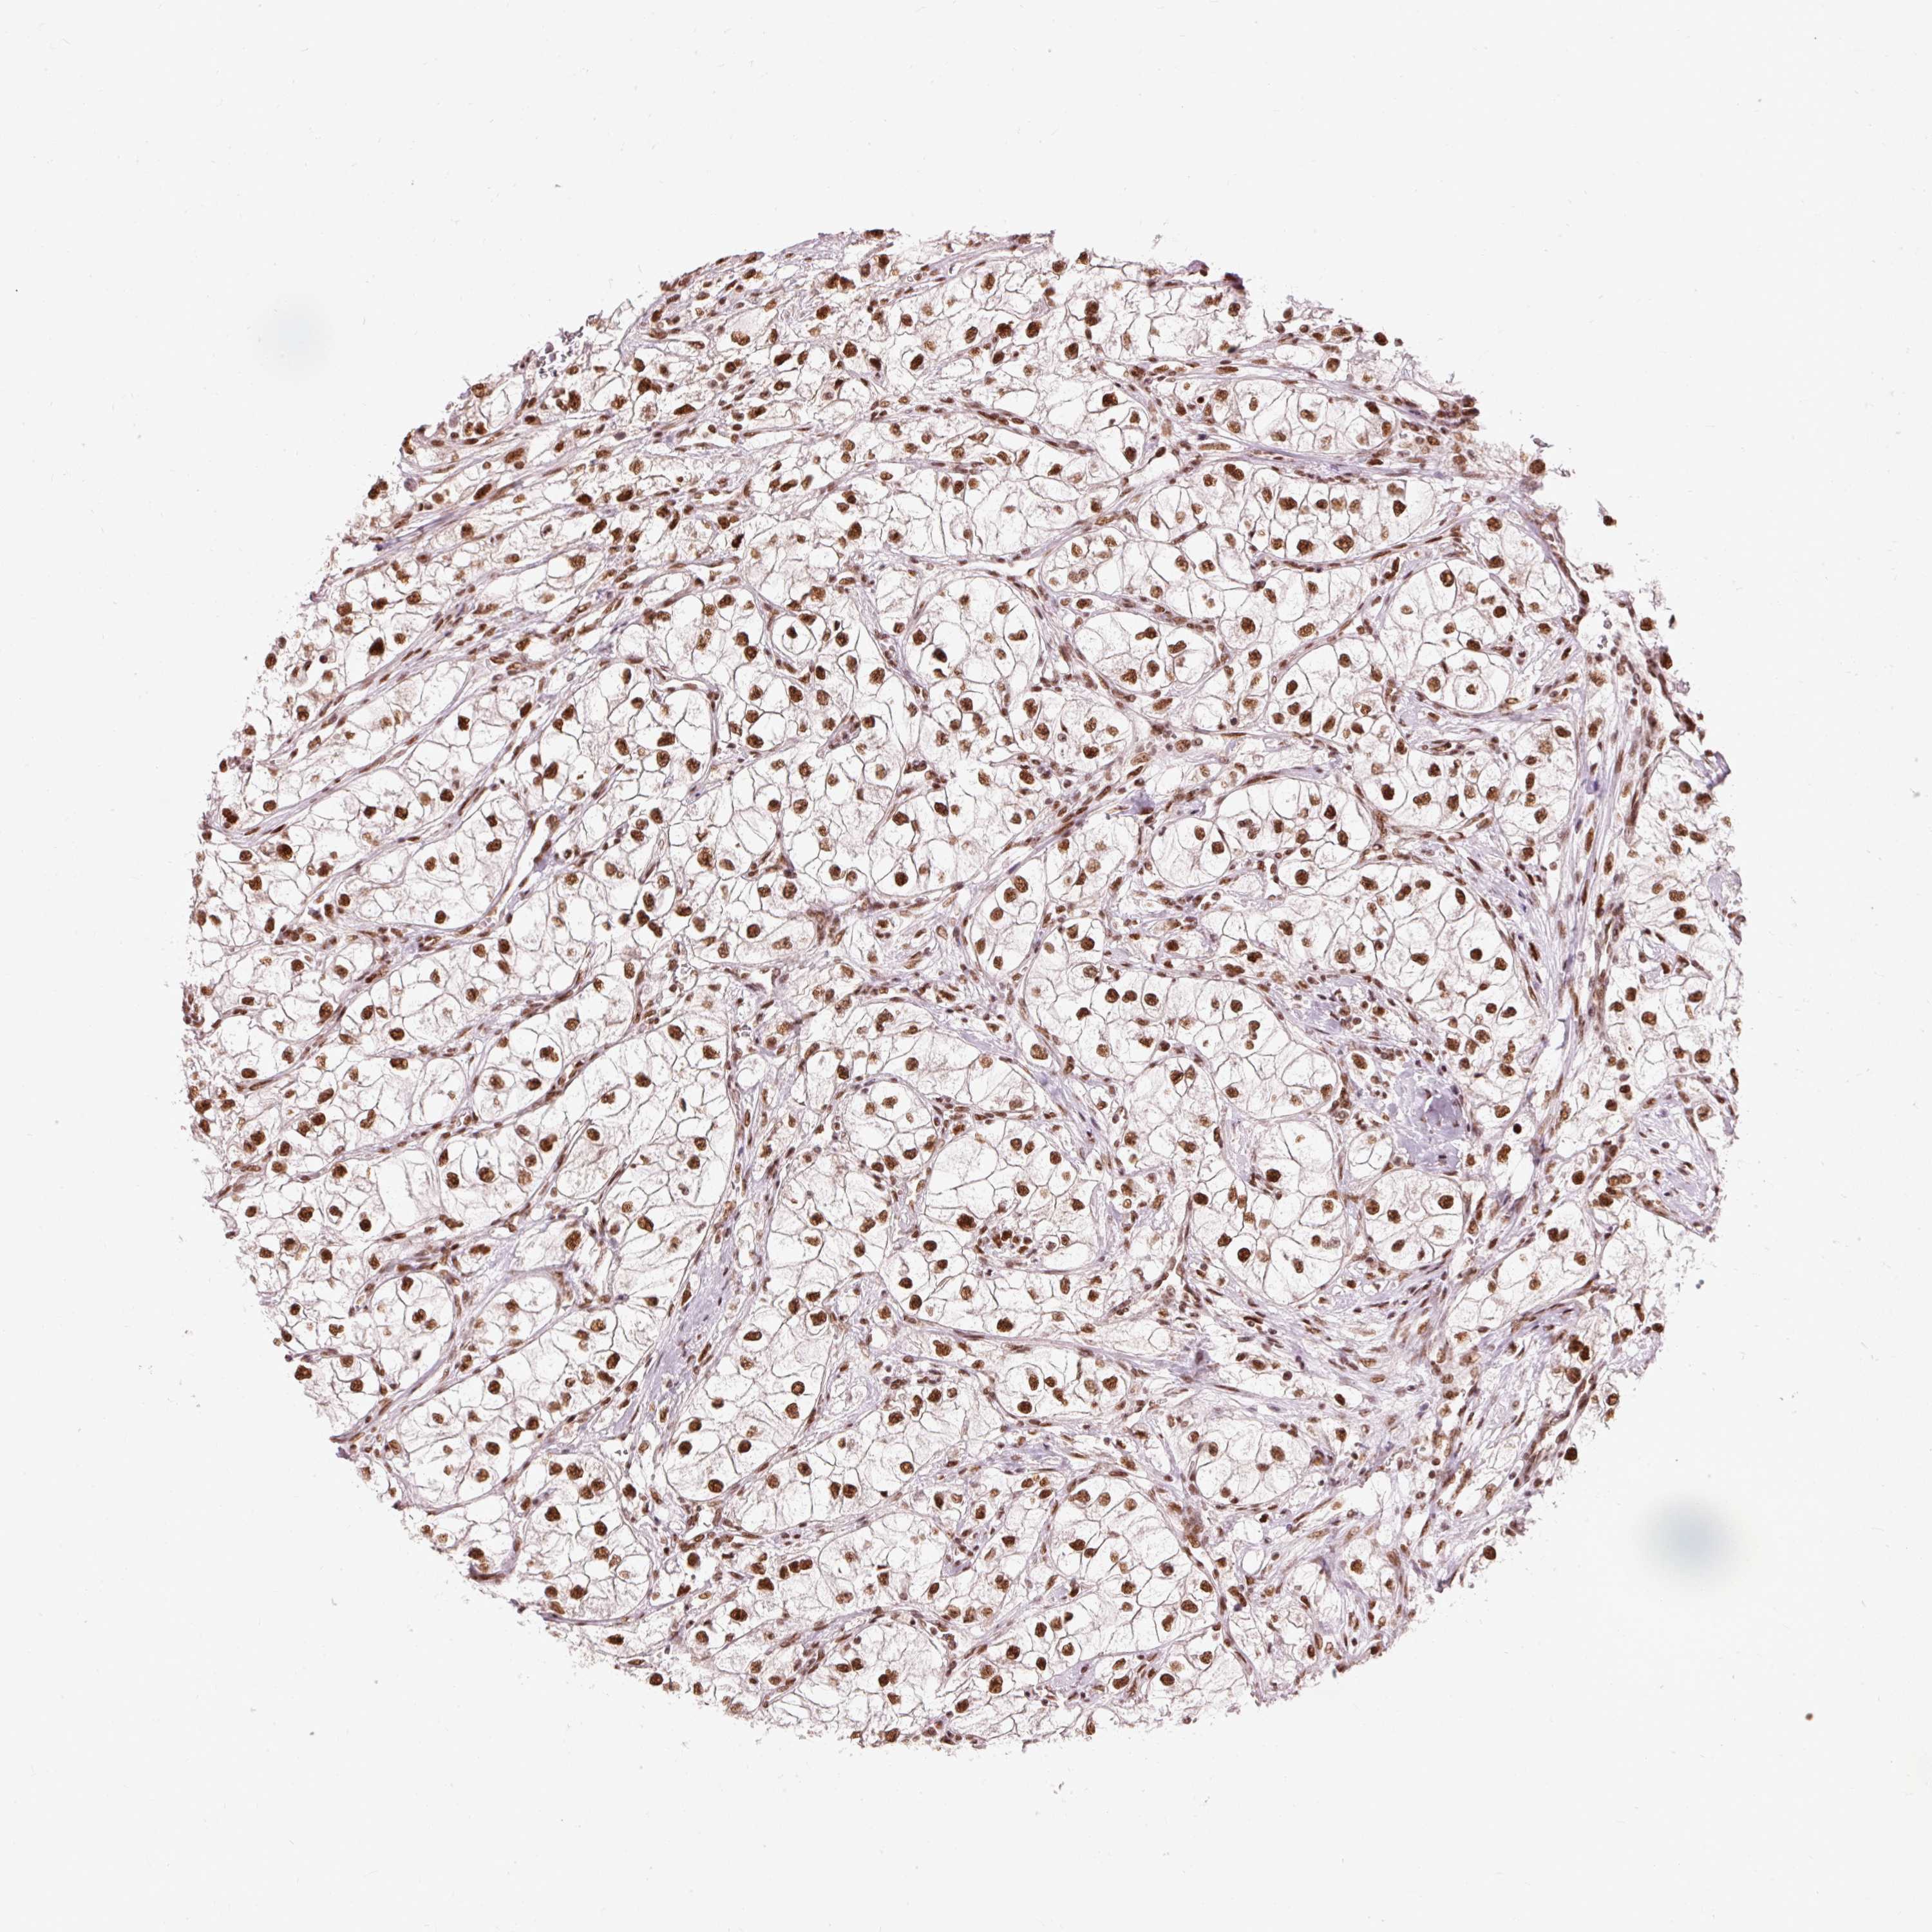

KIDNEY RENAL CLEAR CELL CARCINOMA (VALIDATION) - Interactive survival scatter ploti

The Survival Scatter plot shows the clinical status (i.e. dead or alive) for all individuals in the patient cohort, based on the same data that underlies the corresponding Kaplan-Meier plots. Patients that are alive at last time for follow-up are shown in blue and patients who have died during the study are shown in red.

The x-axis shows the expression levels (FPKM) of the investigated gene in the tumor tissue at the time of diagnosis. The y-axis shows the follow-up time after diagnosis (years). Both axes are complimented with kernel density curves demonstrating the data density over the axes. The top density plot shows the expression levels (FPKM) distribution among dead (red) and alive patients (blue). The right density plot shows the data density of the survived years of dead patients with high and low expression levels respectively, stratified using the cutoff indicated by the vertical dashed line through the Survival Scatter plot. This cutoff is automatically defined based on the FPKM cutoff that minimizes the p-score. The cutoff can be changed by dragging the vertical line or by entering a cutoff value in the square labeled "Current cut-off".

Under the Survival Scatter plot the p-score landscape (black curve; left axis) is shown together with dead median separation (red curve; right axis). Dead median separation is the difference in median mRNA expression between patients who have died with high and low expression, respectively. It is calculated as follows: median FPKM expression of dead patients with high expression - median FPKM expression of dead patients with low expression. This is intended to aid the user in visually exploring custom cutoffs and the associated p-scores and dead median separation.

Individual patient data is displayed and can be filtered by clicking on one or more of the category buttons on the top of the page. Categories describing expression level and patient information include: high, low, alive, dead, female, male and tumor stages. The scale of the x-axis can be toggled between linear and log-scale by clicking on the "x log" button. Mouse-over function shows TCGA ID, patient information and mRNA expression (FPKM) for each patient.

& Survival analysisi

Kaplan-Meier plots summarize results from analysis of correlation between mRNA expression level and patient survival. Patients were divided based on level of expression into one of the two groups "low" (under cut off) or "high" (over cut off). X-axis shows time for survival (years) and y-axis shows the probability of survival, where 1.0 corresponds to 100 percent.

ZBTB44 is validated prognostic, high expression is favorable in Kidney Renal Clear Cell Carcinoma (validation)

Best expression cut offi

Based on the FPKM value of each gene, patients were classified into two groups and association between prognosis (survival) and gene expression (FPKM) was examined. The best expression cut-off refers the FPKM value that yields maximal difference with regard to survival between the two groups at the lowest log-rank P-value. Best expression cut-off was selected based on survival analysis .

When clicking on this number, the vertical dashed line indicating cut-off, the interactive survival plot, and the Kaplan-Meier curve will be adjusted to show results based on the best expression cut-off.

: 24.27

Average pTPM 22.5

Number of samples 100